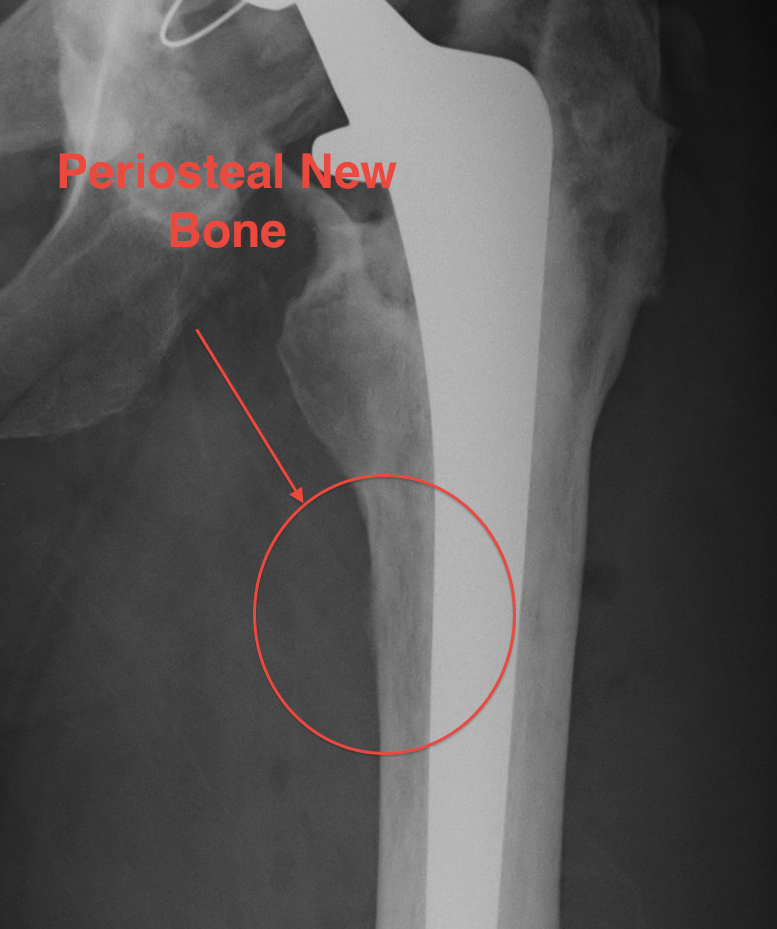

X-ray

1. Progressive radiolucent lines / rapid lysis

2. Focal osteolysis with endosteal scalloping

3. Periosteal new bone

- pathognomonic of infection

- usually at junction meta / diaphysis on medial side

- uncommon

Femoral stem lysis Acetabular lysis